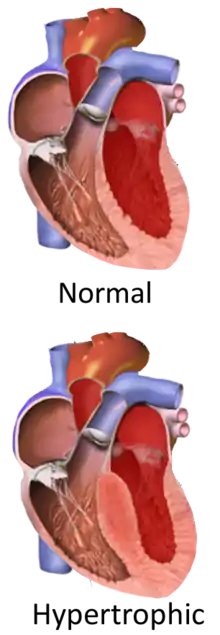

Hypertrophic cardiomyopathy (HCM, or HOCM when obstructive) is a condition in which muscle tissues of the heart become thickened without an obvious cause.[8] The parts of the heart most commonly affected are the interventricular septum and the ventricles.[10] This results in the heart being less able to pump blood effectively and also may cause electrical conduction problems.[3] Specifically, within the bundle branches that conduct impulses through the interventricular septum and into the Purkinje fibers, as these are responsible for the depolarization of contractile cells of both ventricles.[11]